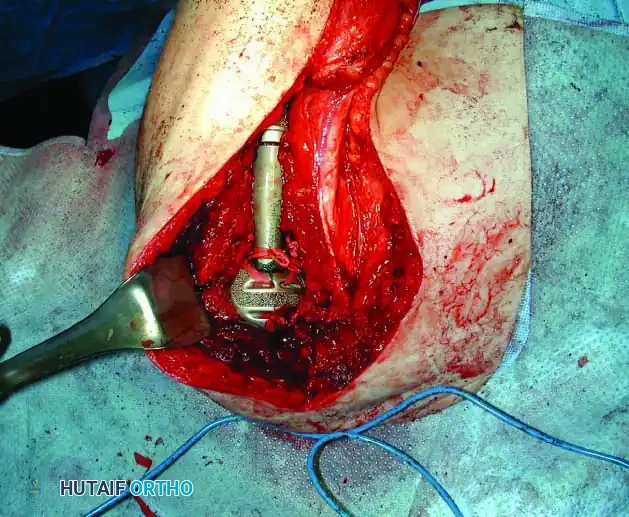

3. Endoprosthetic Arthroplasty: Modular megaprostheses offer immediate stability and rapid rehabilitation.

4. Allograft-Prosthetic Composite (APC): Combines the immediate fixation of a prosthesis with the biologic soft-tissue attachment potential of an allograft.

Clinical Pearl: When utilizing an Allograft-Prosthetic Composite (APC), step-cut osteotomies at the host-allograft junction combined with rigid plate fixation significantly increase rotational stability and union rates compared to transverse osteotomies.

Intraoperative Imaging and Margin Assessment

Continuous intraoperative assessment using fluoroscopy and frozen section pathology is mandatory. The following images demonstrate various stages of complex upper extremity resections, allograft preparations, and prosthetic implantations across the humerus and elbow joint.